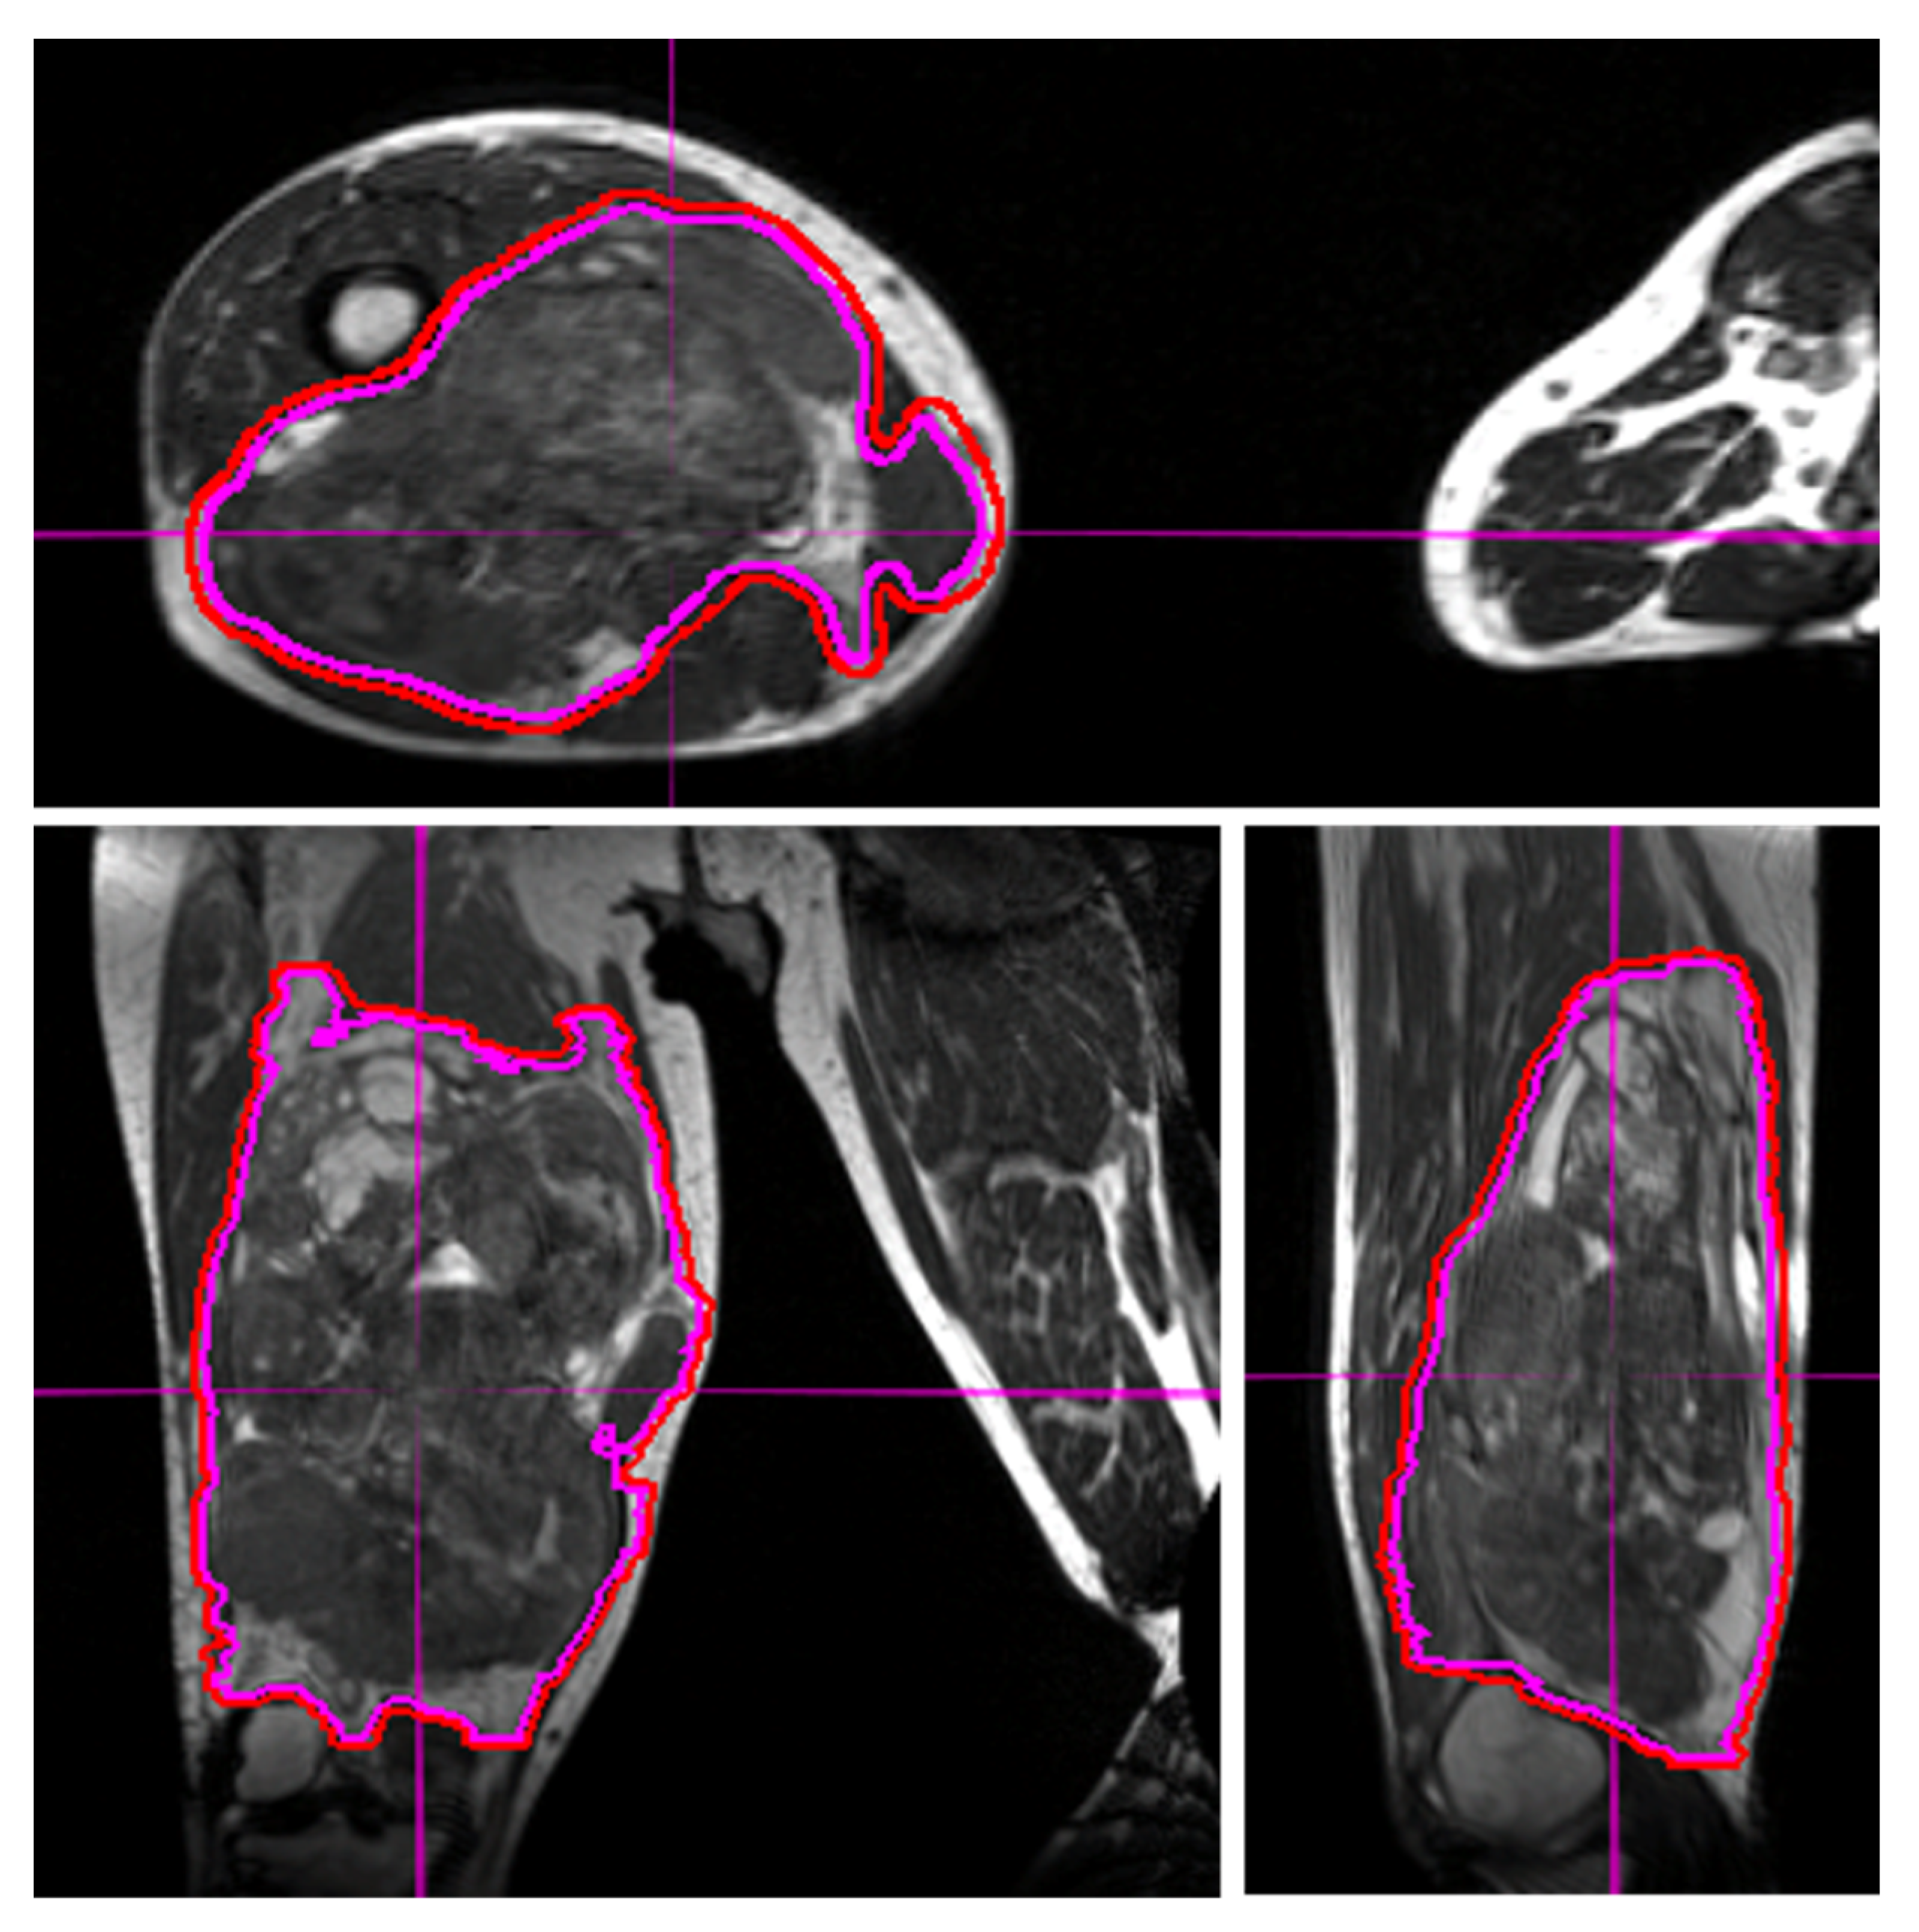

Figure 1. Visualization of an STS and normal tissues in the lower extremity using the 3D True Fast Imaging sequence on MRI-guided linear accelerator for alignment during treatment. The excellent delineation of the tumor and surrounding structures may allow for dose escalation and/or decreased toxicities. The use of daily MRI at set-up improves visualization and allows for smaller margins of expansion from gross tumor volume (magenta line) to planning treatment volume (red line).

Target delineation is crucial to the planning and delivery of radiation therapy. For STS, the target volumes generally consist of the gross disease (in pre-operative and definitive radiation) and areas concerning for microscopic spread of STS. MRI provides superior soft-tissue delineation and multiplanar capability. In addition to target delineation during the radiation contouring and planning process, target delineation during daily treatments is critical. With the use of IMRT and reduced geometric expansions, the need for precision in daily tumor alignment has increased [29]. Extremity STS are among the most challenging tumor sites to align for daily treatment due to the considerable mobility and the multi-axis degrees of freedom associated with these tumors. Molds and immobilization devices can begin to redress this but even with these tools, the use of daily image guidance is often needed to ensure correct tumor alignment during each fraction. Both cone beam CT and surface guidance technology can be used, and may allow for reduced planning target volume (PTV) expansions [30]. However, the ability of MRI to resolve STS tumors from surrounding normal soft tissues makes this a superior modality for daily image guidance of STS radiotherapy (Figure 1).

Daily MRI guidance allowed for the safe delivery of high dose hypofractionated radiation, with all patients having no grade 3 or higher acute toxicities. Understanding of potential late toxicity risks is still developing as clinical experience increases with this approach in patients with STS. For each of these patients, radiotherapy planning scans were acquired on 0.35T MRI (MRIdian, Viewray Inc., Mountain View, CA, USA) using a 3D True Fast Imaging (TRUFI) sequence, with 3 mm slice thickness and 40 cm × 40 cm × 43 cm field of view. A daily fractional MRI was acquired using the same imaging protocol to aid treatment set-up. In the case of the patient with STS of the lower extremity, MRI imaging enabled reproducibility of the positioning required to target the mobile lower extremity while avoiding the contralateral leg (Figure 1). In the case of the patient with STS of the upper extremity, MRI imaging ensured an accurate daily set-up and target delineation both for the planning and for each treatment (Figure 2). In the case of the patient with a retroperitoneal STS, daily MRI visualization allowed for adaptive planning which optimized tumor coverage while reducing dose to nearby organs at risk including bowel and kidney (Figure 3). Daily adaptation requires editing the OARs and/or PTV and re-optimizing the planned dose. Patients undergoing adaptive radiation are scheduled for 60 to 90 min. Based on the size of the lesion, editing contours may take approximately 10–20 min, re-optimization and plan review process may take additional 6–9 min.

In all cases, these large STS tumors were safely treated using hypofractionated radiation therapy. The patients with extremity STS had follow-up imaging demonstrating stable disease without local progression at 3 and 9 months for the cases of lower extremity STS and upper extremity STS, respectively. The patient with retroperitoneal STS had partial response on 6-month follow-up imaging. The use of MRI for daily set-up allowed for 0.3 mm PTV margins to be used for this patient, potentially decreasing the toxicity of the plan while affording confidence in tumor and OAR visualization and dosimetry.